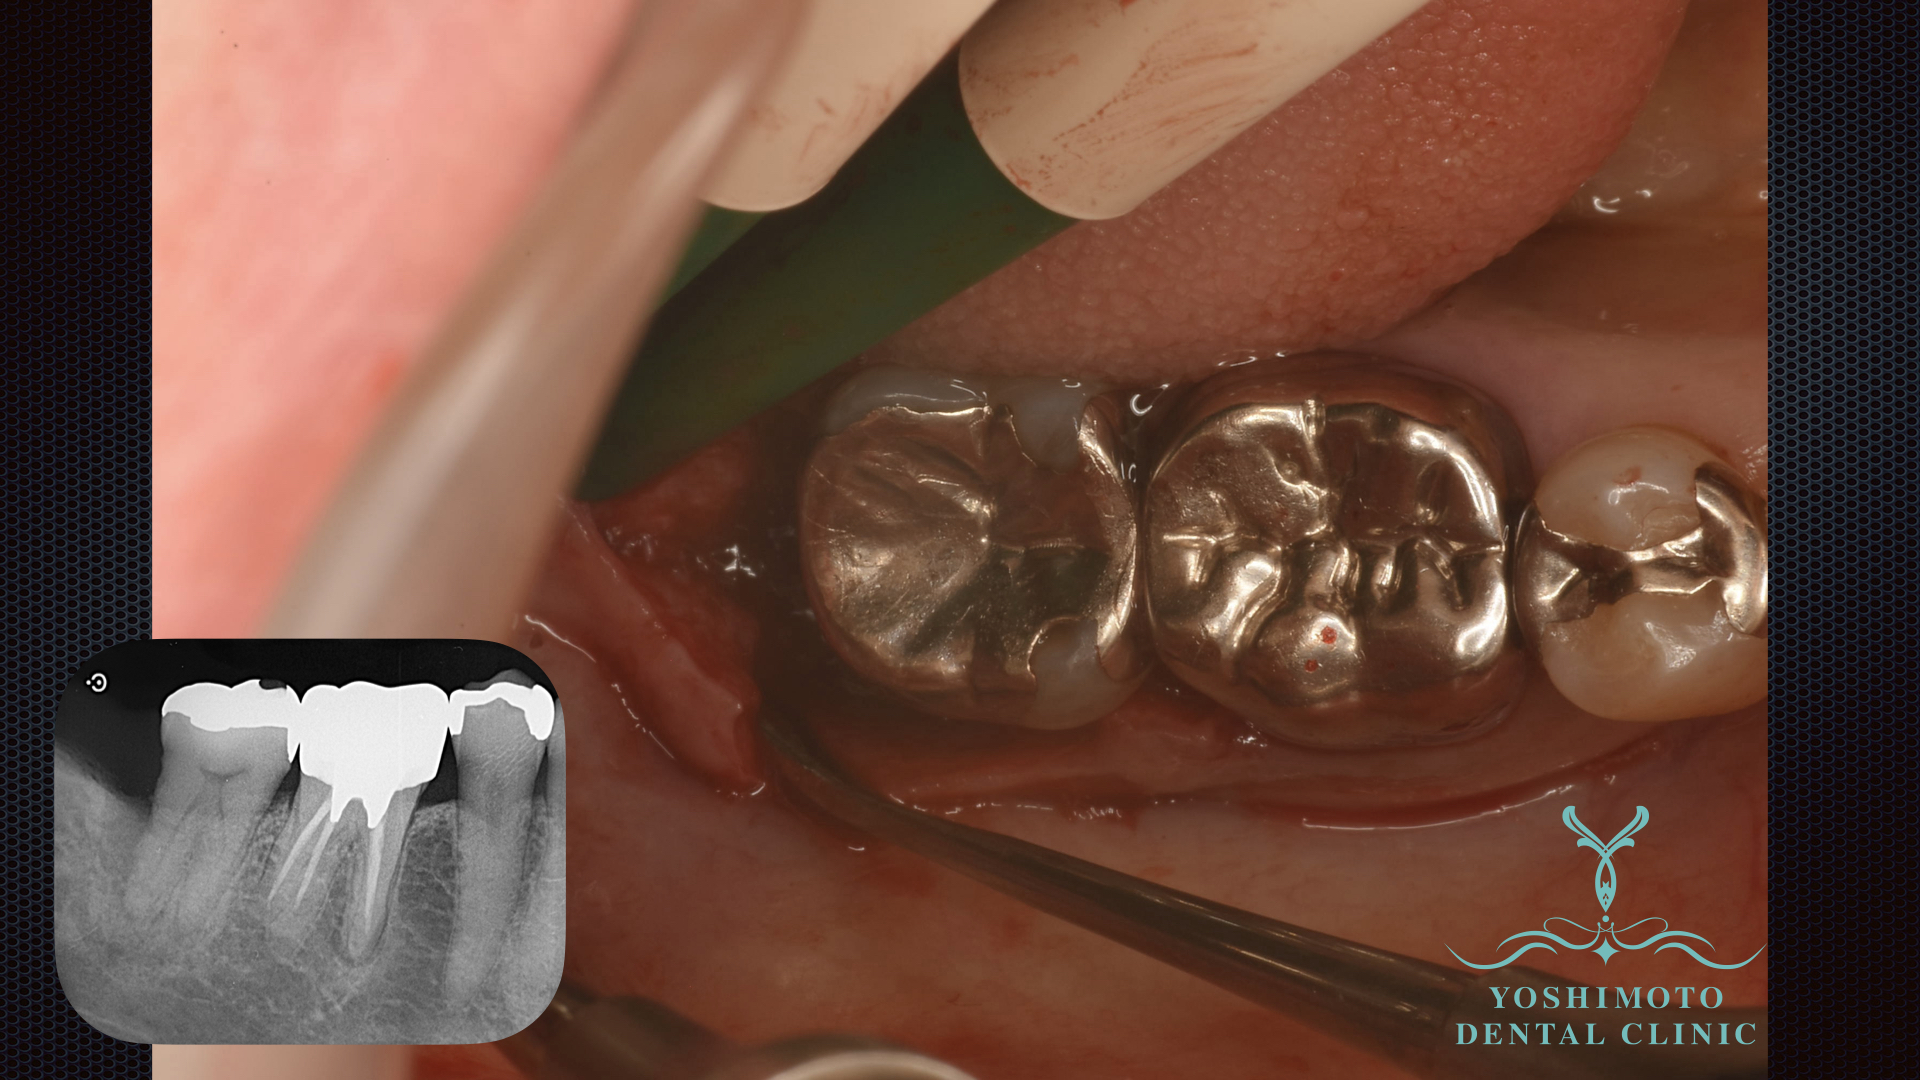

治療の流れとしてレントゲンを撮影し歯肉縁上の歯石やプラークと削除し炎症のコントロールを行います。それでも改善しない場合、歯周外科を行います。

レントゲン所見でも最後臼歯に垂直性の骨吸収が確認されました。

局所麻酔下にて切開を行い、歯肉弁を剥離し徹底的にデブライドメントを行い、リグロスによる歯周組織再生療法を試みました。

リグロスは、歯周病で失われた歯ぐきや骨などの歯周組織を再生させるためのお薬です。

歯周外科治療の際に、欠損した部分に直接使用することで、

歯を支える骨や歯根膜の再生を促進します。